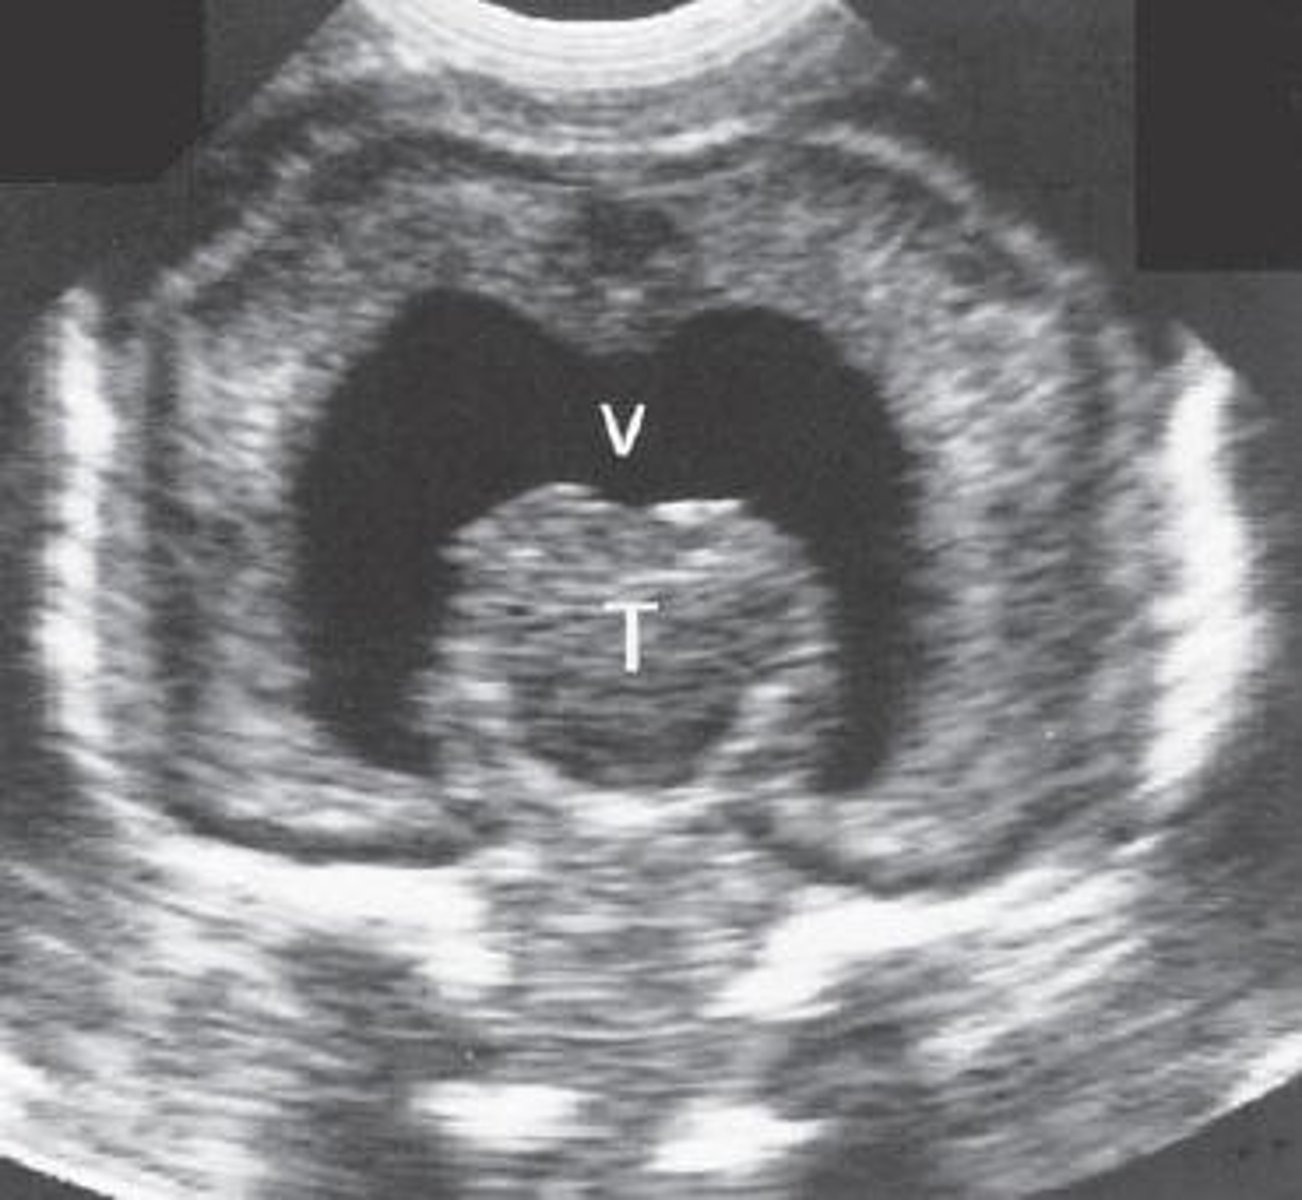

Hydrocephalus

Dilated ventricles

Dangling choroid plexus

Enlarged head

Alobar Holoprosencephaly

Single ventricle

Fusion of thalamus